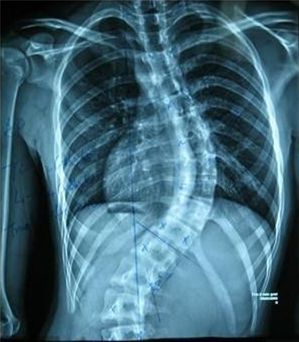

强直性脊柱炎是一种起病隐匿,全身性的发炎性慢性疾病,脊柱关节是强直性脊柱炎的主要侵犯部位,并且病变到一定时期,患者还会产生一些并发症,而泌尿系统疾病就是较为常见的一种强直性脊柱炎并发症。成都治疗强直

成都治疗强直,强直性脊柱炎产生一些并发症.jpg